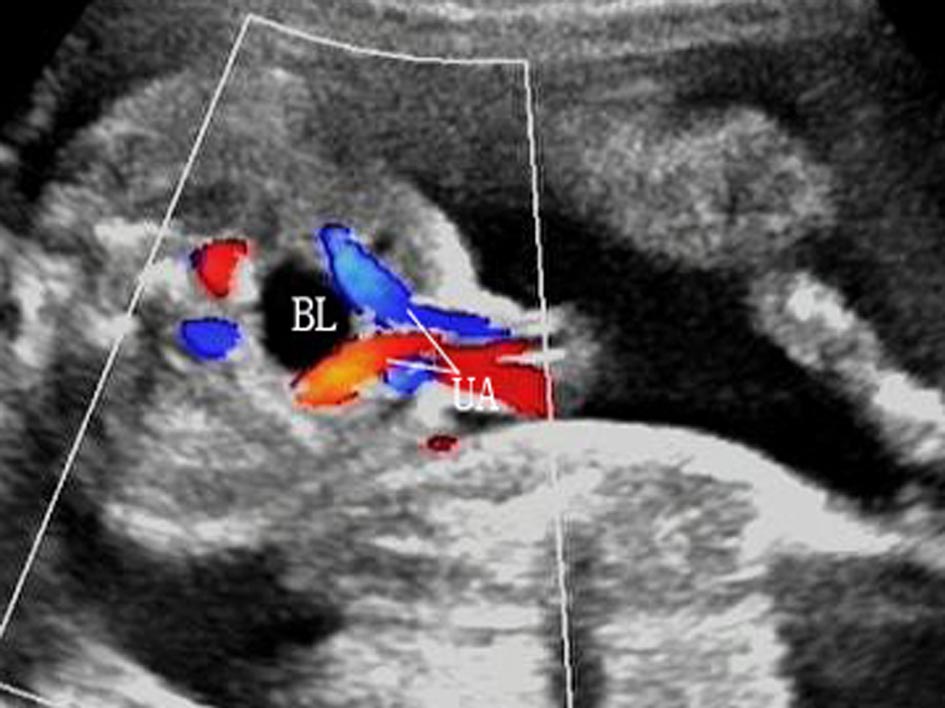

3.膀胱 显示为盆腔内圆或椭圆形无回声区(图7 BL)。正常情况下早孕晚期开始产生尿液,孕13周以后可显示为典型的无回声区,脐动脉腹腔段的显示有助于对评估的辨认。正常膀胱每20~45min充盈和排空一次,孕15周可清晰显示。膀胱容量不定,过度充盈时,要在30~45min后复查以排除尿路梗阻。

图7胎儿膀胱横切面声像图